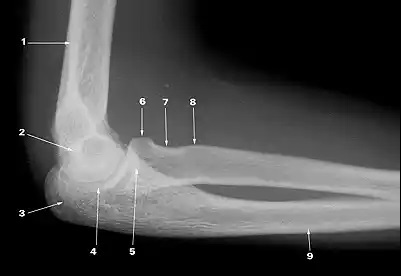

What does 3 indicate?

olecranon process

What does 4 indicate?

trochlear notch

What does 5 indicate?

coronoid process of ulna

What does 1 indicate?

supracondylar ridge

What does 8 indicate?

tuberosity of radius

What does 2 indicate?

trochlea